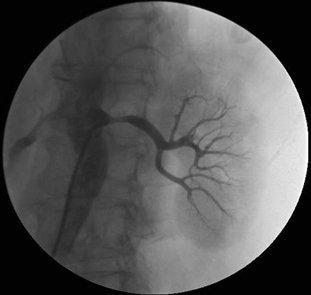

肾动脉造影

相关,介入治疗指征明确,遂行双肾动脉造影进一步评估肾动脉狭窄情况

正常肾造影,动脉期